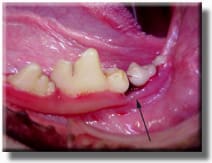

Radiograph reveals severe bone loss and an abscessed tooth hidden beneath the gumline.

Half of the lower jaw bone has been destroyed by infection under the gum line, and the tooth required extraction. This process took years to occur, but was hidden under the gum line, out of view. If this had been caught sooner, the tooth could have been treated.